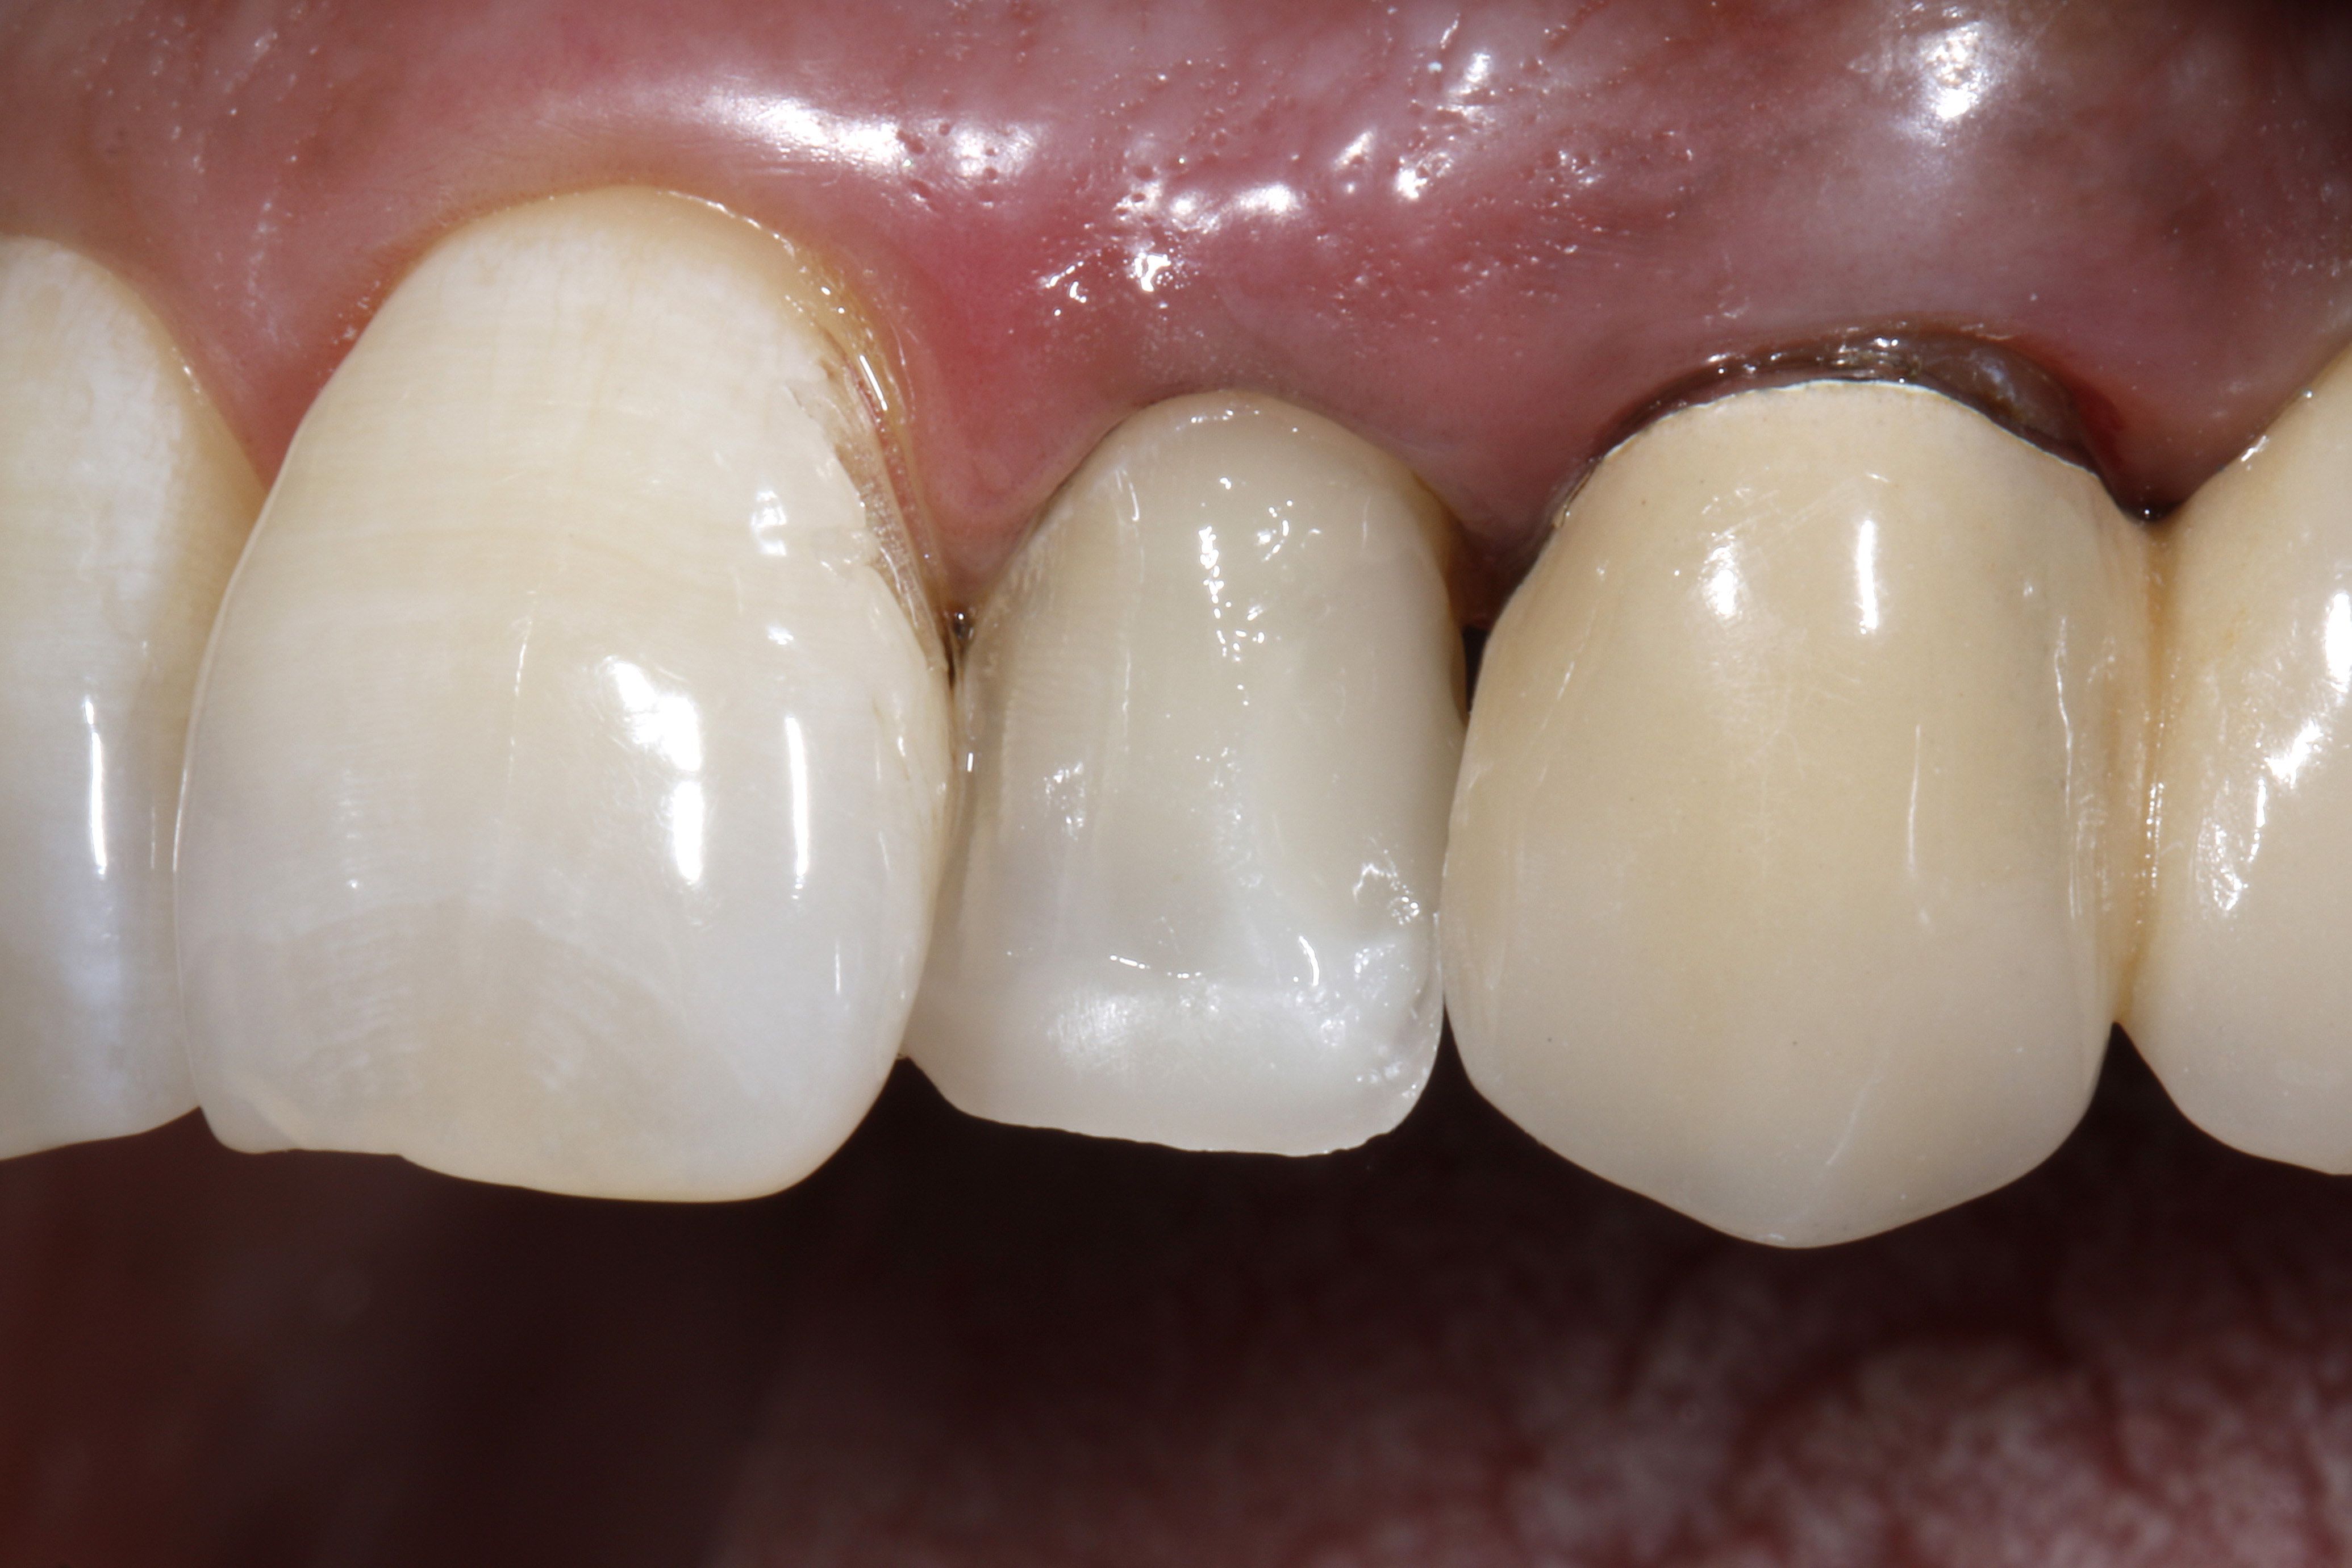

Po nadaniu kształtu, kompozyt utwardzono przez 10 sekund światłem lampy (intensywność światła > 1200 mW/cm²). W drugim etapie zastosowano GrandioSO Unlimited do wypełnienia dystalnej części ubytku i kompozyt ponownie utwardzono (ryc. 18). Następnie nałożono materiał na całą powierzchnię wargową, jako bezpośrednią licówkę kompozytową, aby optycznie przesunąć materiał wargowo, a tym samym uzyskać lepszą pozycję w łuku zębowym (ryc. 19). Krawędzie proksymalne ukształtowano przy użyciu techniki „matrix pull” według Corky'ego Willhite'a (24). Na koniec materiał do wypełnień ponownie utwardzono przez 10 sek.

Bezpośrednią licówkę kompozytową wykończono stosując narzędzia obrotowe i krążki ścierne. Gładką i błyszczącą powierzchnię rekonstrukcji uzyskano za pomocą gumek do kompozytów (Diacomp Twist, EVE Ernst Vetter GmbH, Keltern) (ryc. 20). Efektem zastosowania licówki jest wargowe przesunięcie siekacza bocznego, co znacznie poprawiło jego pozycję w łuku zębowym (ryc. 21). Na koniec na ząb nałożono lakier fluorkowy (Bifluorid 10, VOCO GmbH, Cuxhaven), stosując kulki z gąbki.

Ryc. 20, 21. Efekt końcowy.